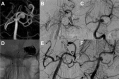

Figure 2

Ruptured aneurysm (A) of the basilar apex that was treated with a WEB DL device in the acute phase. The profile projection in (B) depicts the device with contrast stasis in the mesh. The final result was a small neck remnant (C). A constantly growing aneurysm recurrence. (D) was treated 40 months later using a WEB SL device (E). For protection of the right P1 segment a self-expanding stent (Enterprise 4×16 mm) was placed. Follow-up after 7 months shows a small neck remnant (F).